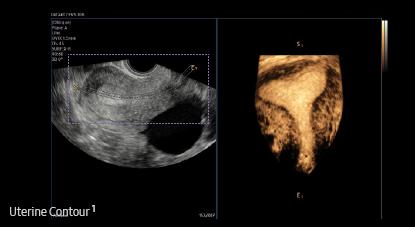

Uterine Contour¹ is a feature to help in identifying uterine malformation. It automatically extracts the centerline and thickness of the curved endometrium and provides a coronal view in 3D, flattened by the centerline. In addition, uterine malformation classification are reported according to the ESHRE/ ESGE or ASRM guideline selection.

* ESHRE/ESGE : The European Society of Human Reproduction and Embryology / The European Society for Gynaecological Endoscopy

* ASRM : The American Society for Reproductive Medicine